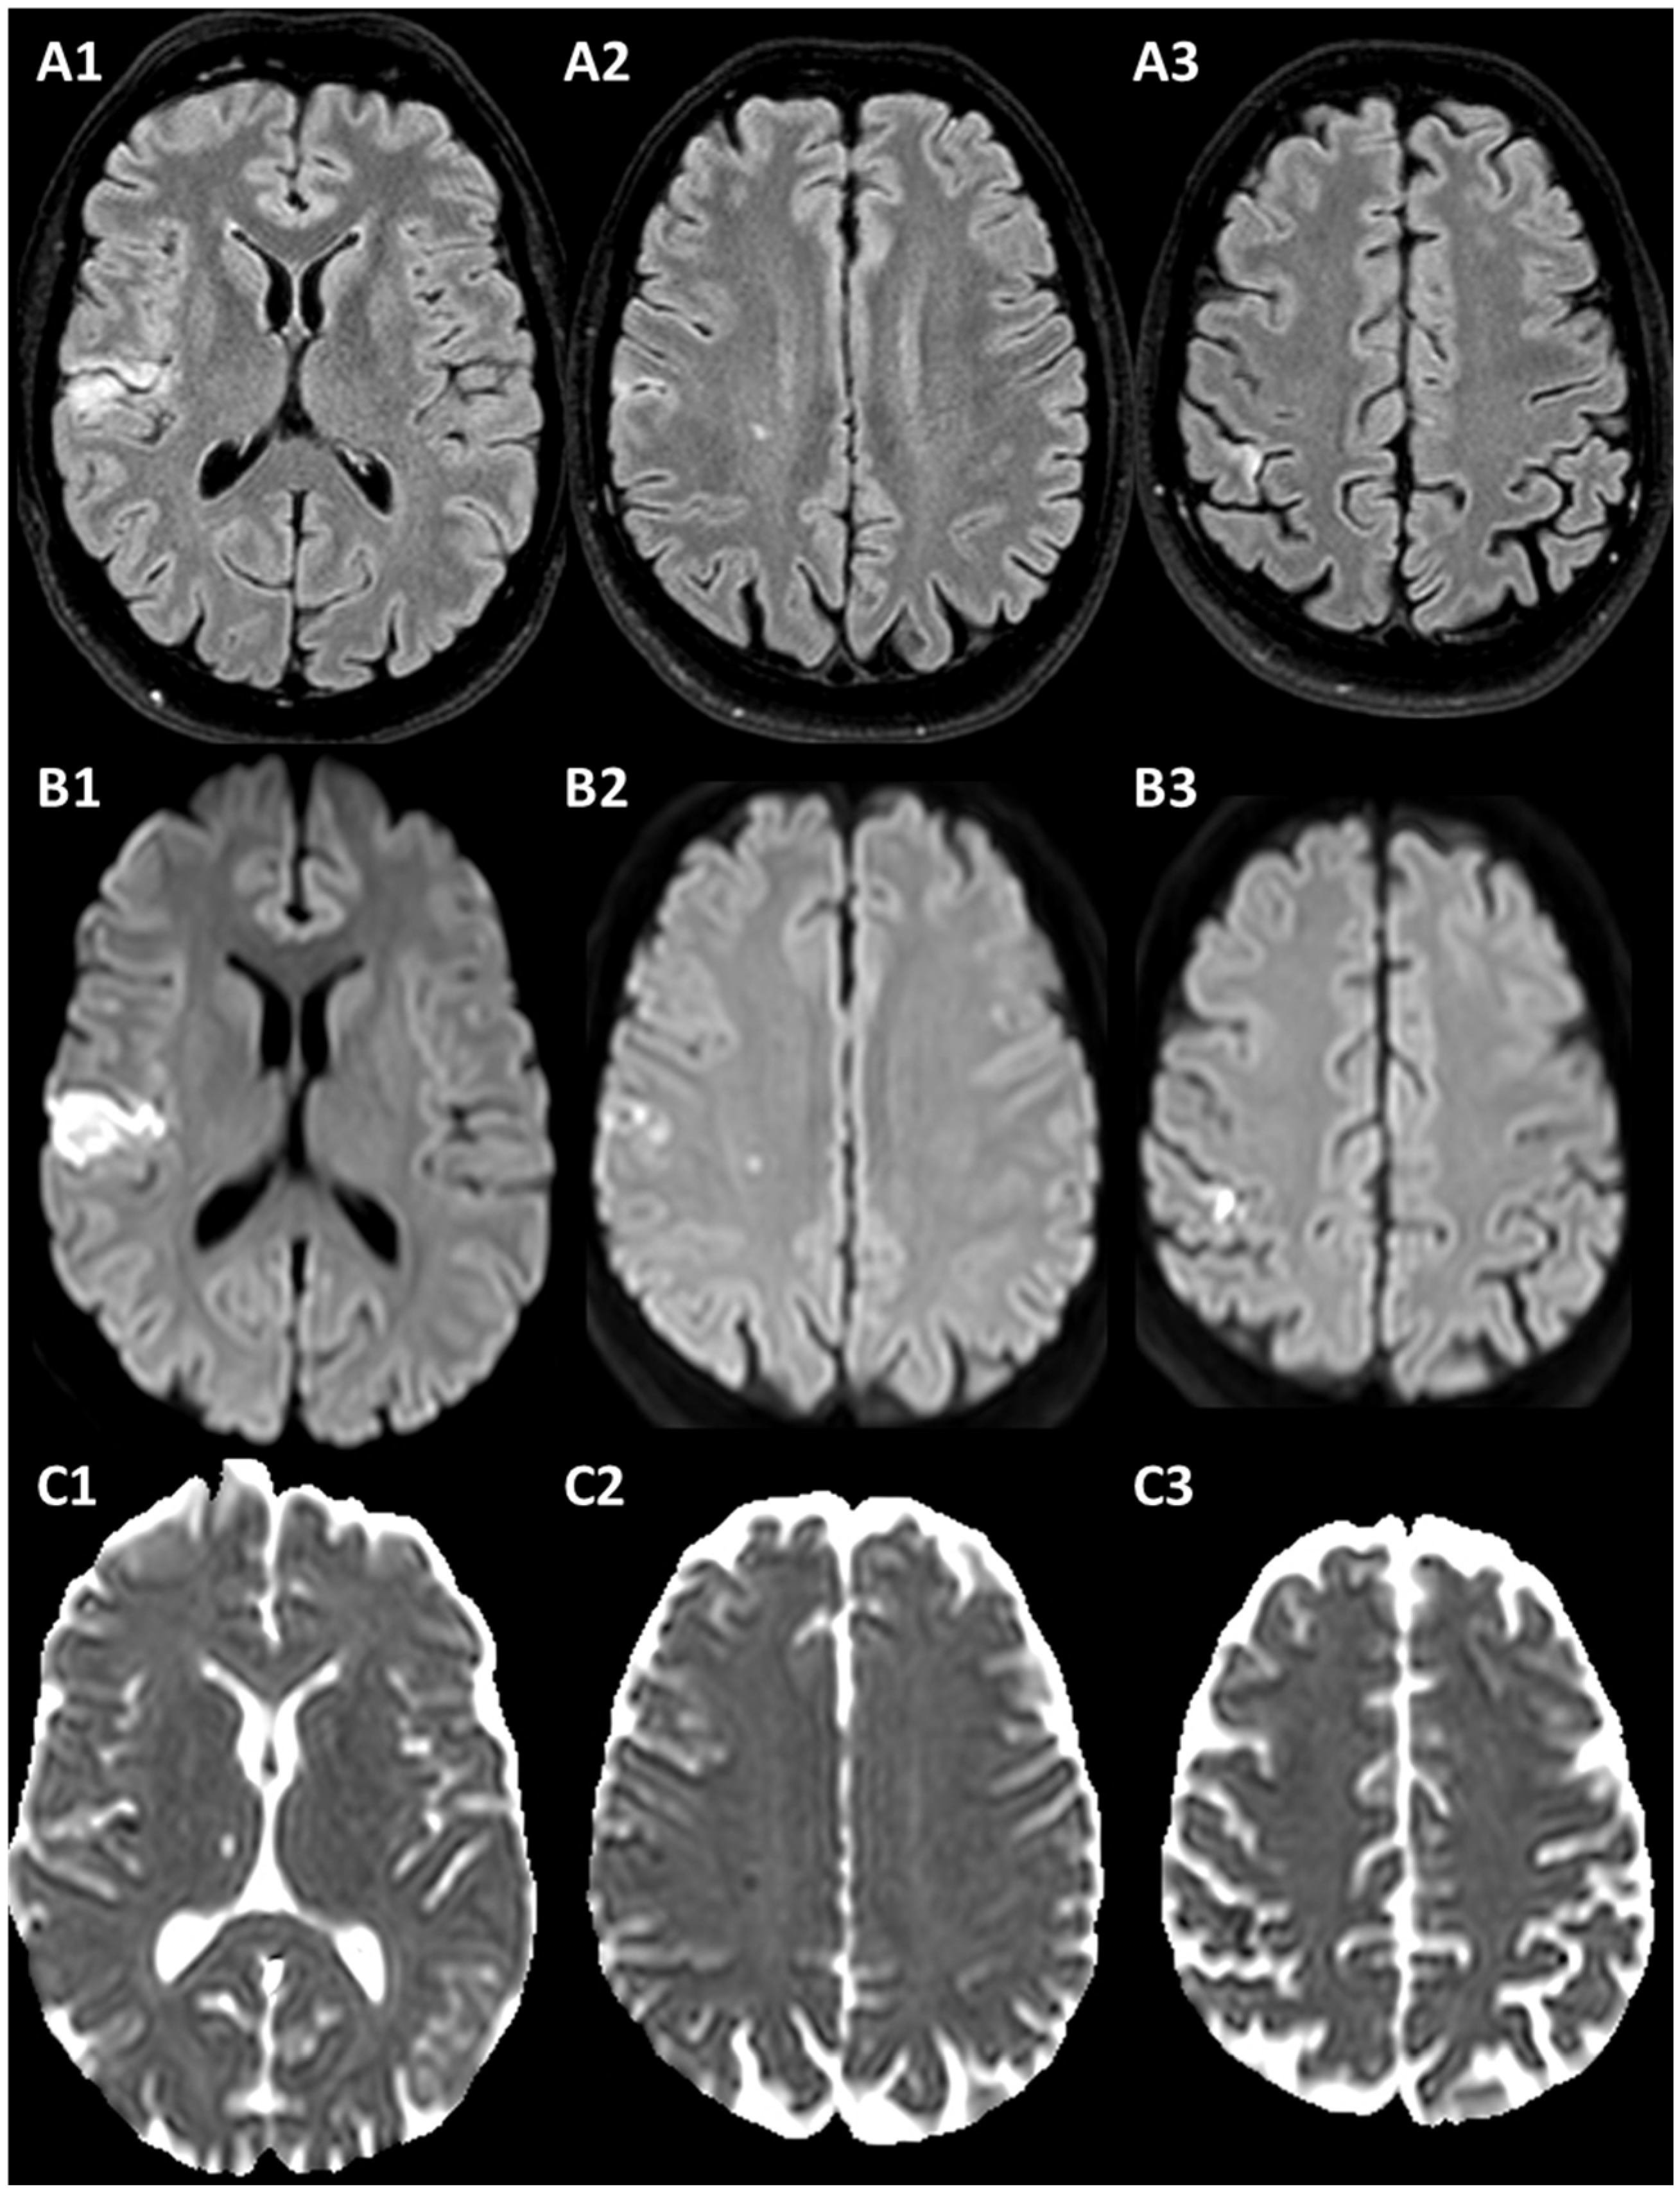

3.1. Case 1

3.2. Case 2